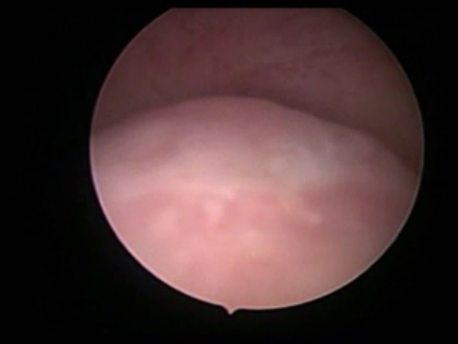

Endoscopy involves placing a small telescope into the human body through tiny incisions (3-5mm). The telescope can be placed into the abdomen via small tubes called ports (laparoscopy) or inside the uterus through the mouth of the uterus or cervix (hysteroscopy).